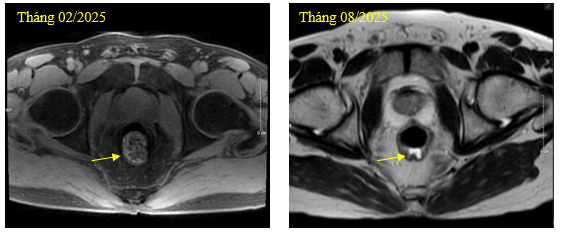

- Chụp cộng hưởng từ vùng chậu: Trực tràng giữa dày thành không đều quanh chu vi, dày nhất 10mm, trên đoạn dài ~34mm ngấm thuốc không đồng nhất sau tiêm (giảm kích thước), lân cận có vài hạch, hạch lớn nhất ~13x10mm (không thay đổi).

Hình 3. Hình ảnh u trực tràng trung bình trước và sau điều trị